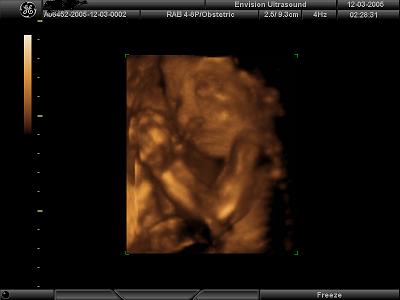

4D Ultrasound pics

We went to Envision in NJ yesterday to get our 4D ultrasound done for our 7 year wedding anniversary. It was the best gift we have ever given to each other!! Our little girl looks just like daddy but has mommys one dimple on her left cheek She is so beautiful and was playing with her umbilical cord the whole time trying to shove it in her little mouth. It was so fun to watch!! I would highly recommend getting it done. I posted my 4 fave pics out of 35 that we came home with and a lovely DVD set to music. Image Attachment(s):